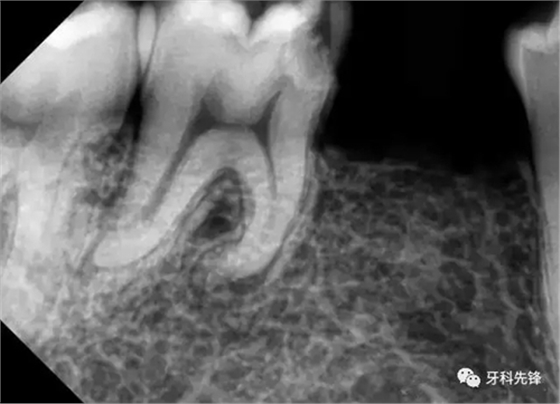

檢查: 男,23歲。46近中鄰咬合面齲洞,探痛(+),叩診叩痛(+),無病理性松動,X-ray示近中鄰咬合面暗影,近髓腔,牙根彎曲,根尖無明顯暗影,牙周膜增寬。

診斷:46急性牙髓炎